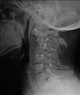

Atlantoaxial dislocation

Atlanto-occipital dislocation, orthopedic decapitation, or internal decapitation describes ligamentous separation of the spinal column from the skull base. It is possible for a human to survive such an injury; however, only 30% of cases do not result in immediate death. [Source: Wikipedia ]